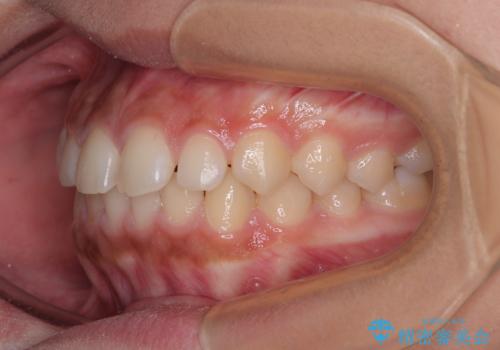

気になるすきっ歯を短期間で改善 インビザライン矯正

- 前歯の隙間を気にして来院された患者様です。

口元の突出感があり、小臼歯4本を抜歯して口元を引っ込める矯正治療も提案しましたが、本人は口元の突出感は気になっていないとのことで、インビザラインにて隙間やデコボコを改善することとしました。

軽度の歯列不正であったため、廉価版のインビザライン・モデレートパッケージにて治療を終えることができました。